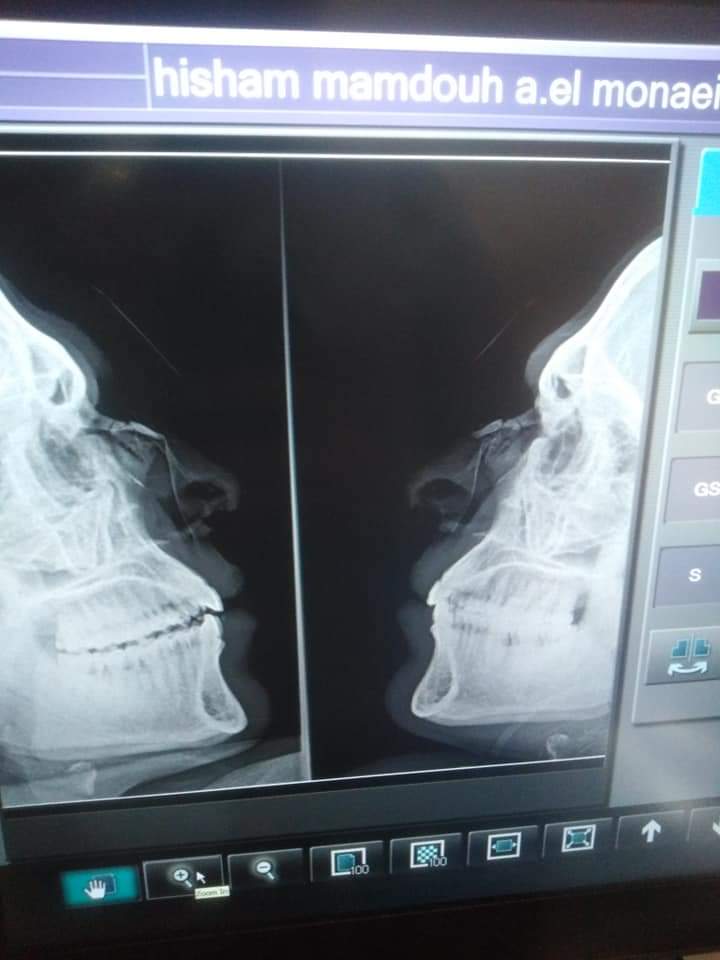

حارس كوم حمادة المعتدى عليه

وتعود الواقعة لإشهار حكم المباراة البطاقة الحمراء في وجه لاعب فريق الزعفران، عقب اعتدائه على حارس مرمى فريق كوم حمادة، بشكل عنيف تسبب في كسر بالأنف، ليتم نقل الحارس إلى أقرب مستشفى لإجراء الإشاعة اللازمة والاطمئنان على سلامته.